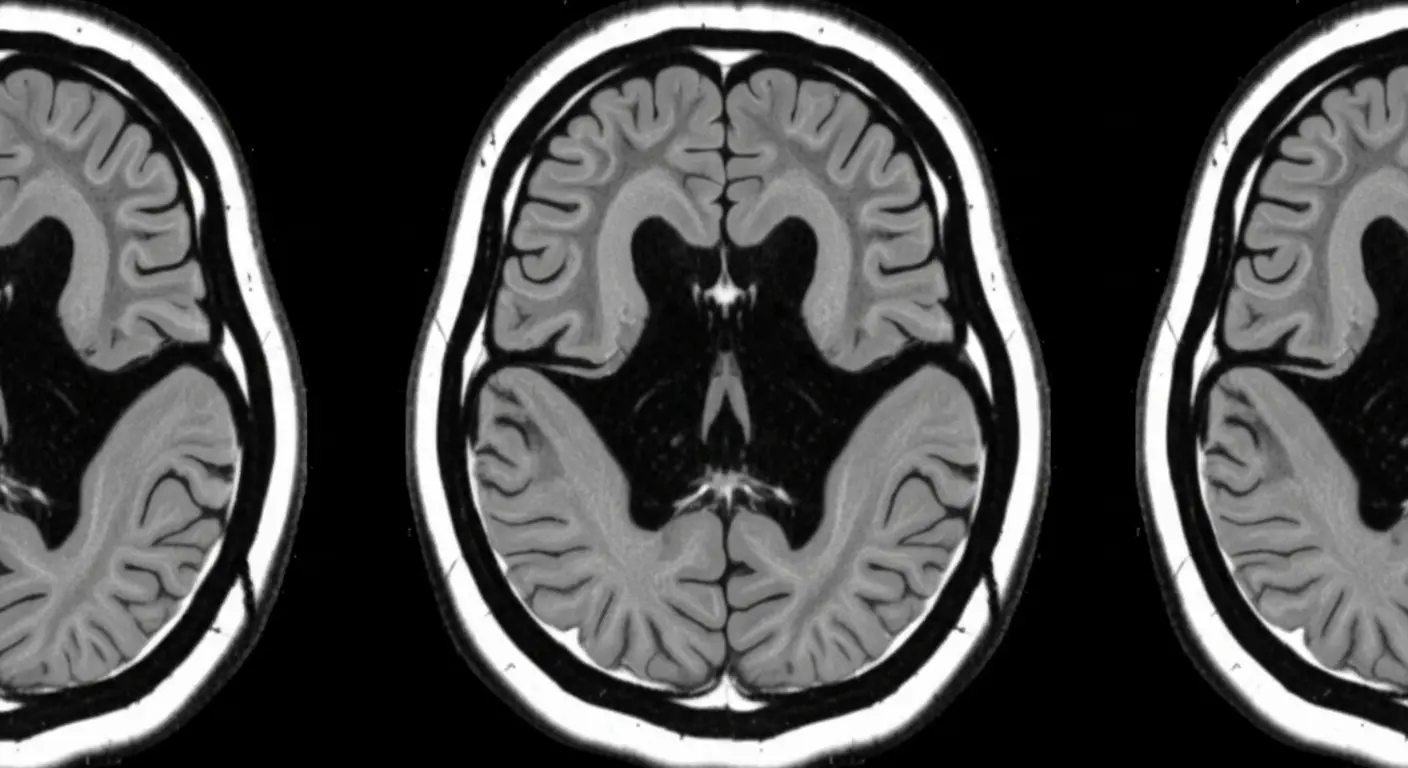

Researchers at Penn State are pioneering a new approach to Alzheimer’s and dementia detection, harnessing the power of artificial intelligence to analyze speech patterns. With over 7 million Americans aged 65 and older currently suffering from Alzheimer’s disease—a 2025 figure from the Alzheimer’s Association—earlier diagnosis is critical for improved patient outcomes. Their work, recently published in the Journal of Alzheimer’s Disease Reports and Frontiers in Aging Neuroscience, proposes a framework that could detect cognitive decline years before traditional methods. “Traditional dementia screening tools are paper-based, subjective and resource-intensive…lacking sensitivity to subtle cognitive changes,” explains Hui Yang, Gary and Sheila Bello Chair in Industrial and Manufacturing Engineering at Penn State, highlighting the urgent need for scalable AI solutions in the face of a growing geriatric care crisis.

A new approach to detecting early signs of neurodegenerative diseases centers on the nuanced analysis of human speech, potentially offering a significant leap forward in cognitive care. Researchers are leveraging artificial intelligence to identify subtle linguistic shifts often missed by traditional, paper-based screening methods. According to a 2025 report from the Alzheimer’s Association, over 7 million people aged 65 and older in the United States currently live with Alzheimer’s disease, highlighting the urgent need for earlier and more accurate diagnostic tools.